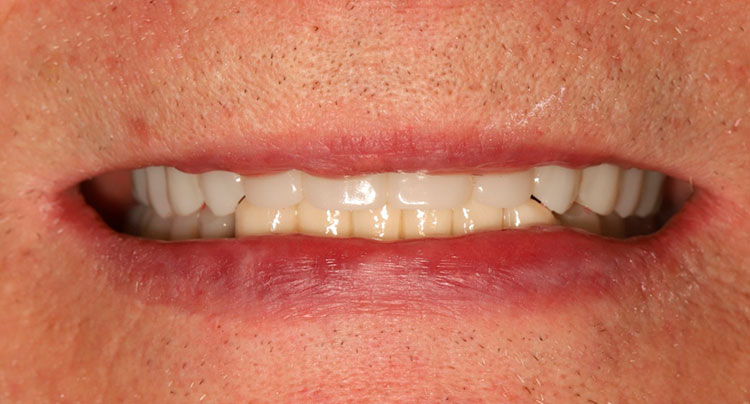

Через 5 дней сняты швы, установлен временный пластмассовый мостовидный протез, проведена коррекция.

Через 4 месяца пациенту установлен постоянный циркониевый мостовидный протез на титановой балке. Состояние костной ткани хорошее. Состояние десны удовлетворительное, жалоб нет.